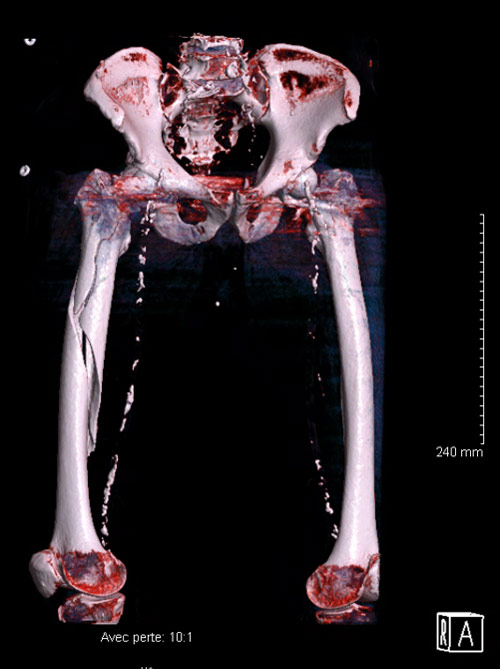

A 71-year-old male, who underwent a right Total Hip Arthroplasty (THA) 12 years ago and a left THA 5 years ago for hip osteoarthritis, recently experienced a fall while walking. Which classification system is appropriate for categorizing the fracture observed in the imagery, and what specific grade? Considering the patient's age, history of bilateral THA, and the nature of the fracture, how would you approach the management of this condition?

Imagery

Peri prostetic femoral fracture - Imagery

Which classification allows us to categorize this fracture and what is its grade?

• ✔️Vancouver classification grade B2